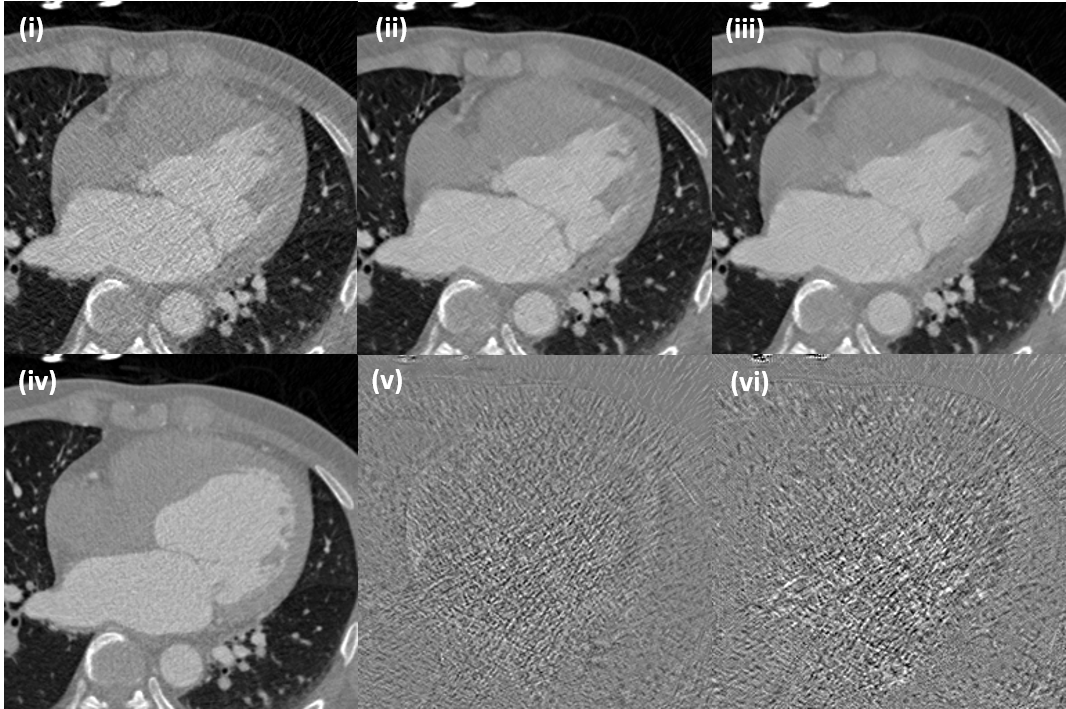

The dataset does not have paired reference data so that quantitative comparison using PSNR and SSIM is not possible. Therefore, we qualitatively compared denoising performance. Intensity of the CT images is shown (-1024, 1024) [HU], whereas the difference images are shown in (-200, 200) [HU] for 20% dose.

Fig. 11(a) shows denoising result by various methods. Note that the target is not perfectly aligned with the input, since there are no perfectly aligned high-dose images in in vivo experiments. Still, the visual inspection and the difference images from the input shows that our cycle-free CycleGAN with an invertible generator removes various noise components more uniformly than the AdaIN-based CycleGAN method without incurring any structural distortion. In Fig. 11(b), SDCT images can be successfully converted to noisy images. Even if the proposed method does not apply any discriminator or loss for inverse mapping, our method adds proper noise level to SDCT.